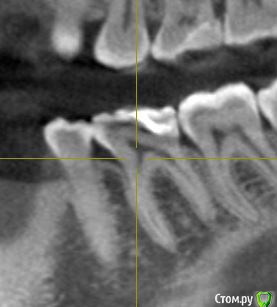

Сделала КЛКТ для того чтобы посмотреть насколько близко к пульпе располагается пломба. Однако материал данной реставрации оказался нерентгеноконтрастным. Так что только такой снимок зуба.

Также прилагаю снимок до лечения (там реставрация видна).

post-57670-0-35233500-1559651003_thumb.jpg